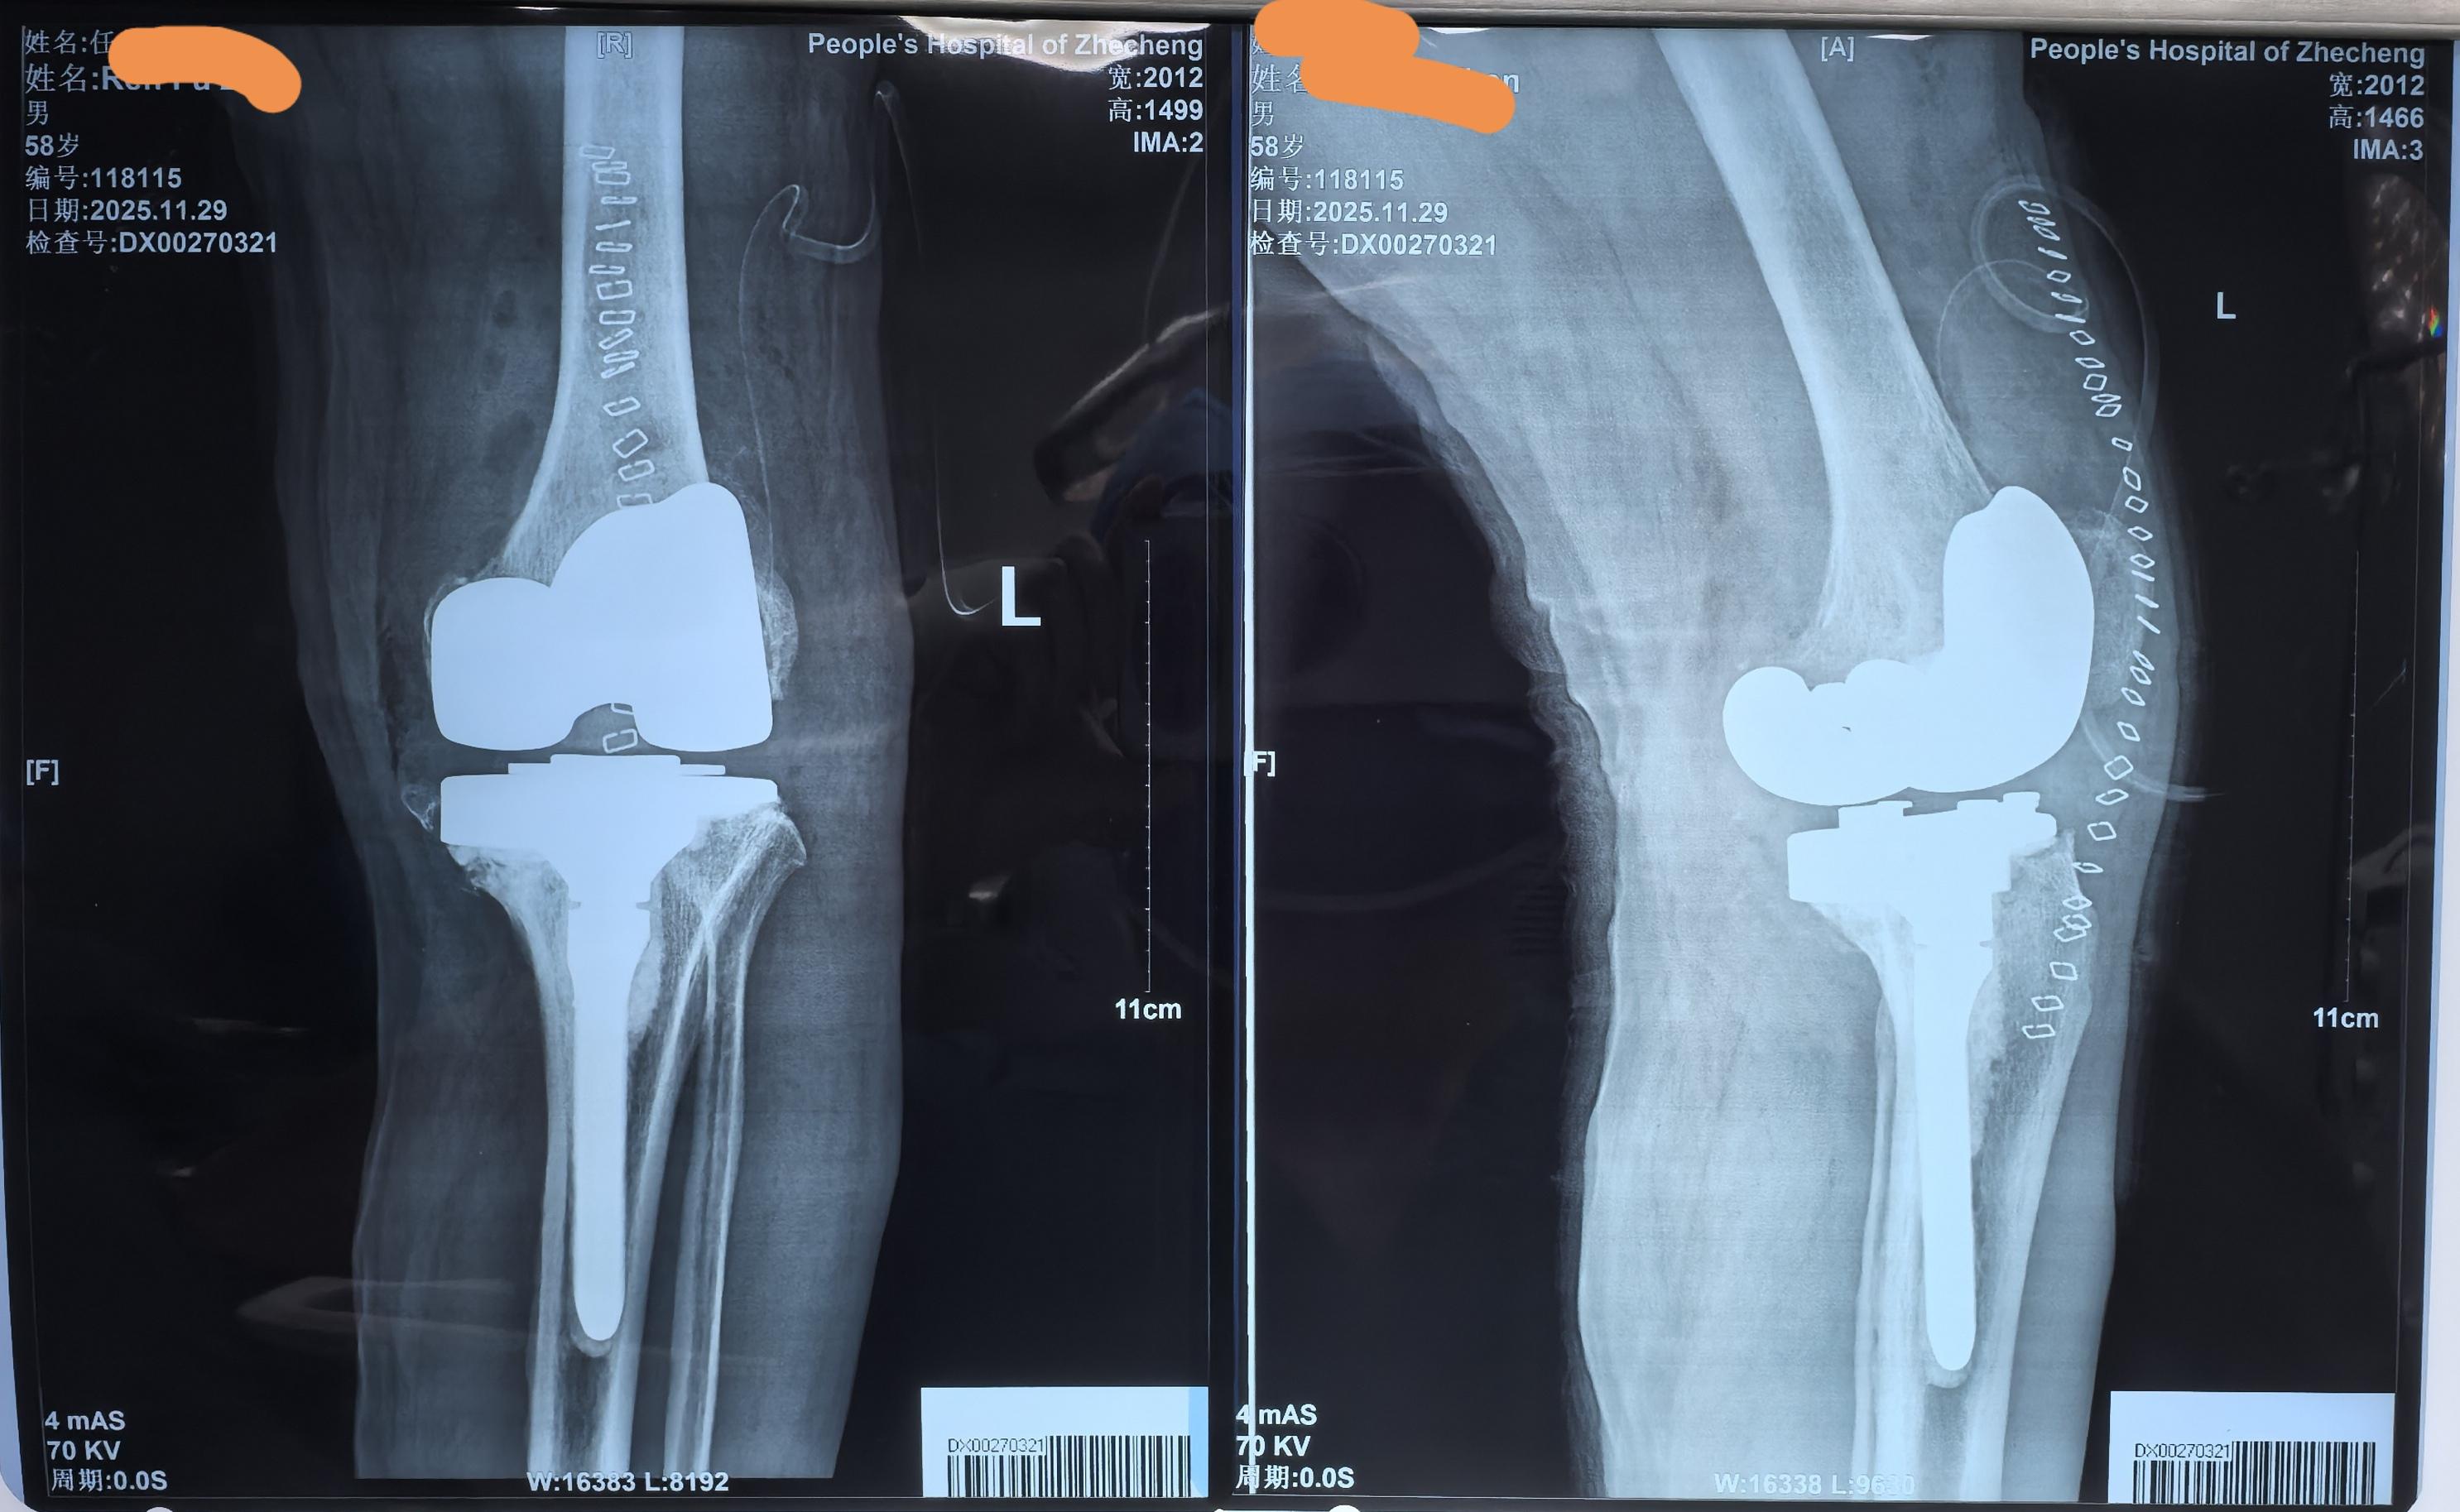

单髁置换术后全膝翻修。单髁置换术后假体松动,双侧全膝翻修。还是那句话,UKA一定严格把握适应症,掌握手术技术要点,才能用的长久。